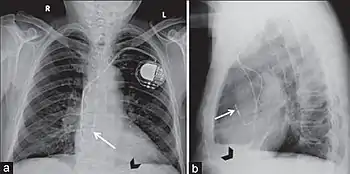

A pacemaker may be implanted whilst a person is awake using local anesthetic to numb the skin with or without sedation, or asleep using a general anesthetic.[25] An antibiotic is usually given to reduce the risk of infection.[25] Pacemakers are generally implanted in the front of the chest in the region of the left or right shoulder. The skin is prepared by clipping or shaving any hair over the implant site before cleaning the skin with a disinfectant such as chlorhexidine. An incision is made below the collar bone and a space or pocket is created under the skin to house the pacemaker generator. This pocket is usually created just above the pectoralis major muscle (prepectoral), but in some cases the device may be inserted beneath the muscle (submuscular).[26] The lead or leads are fed into the heart through a large vein guided by X-ray imaging (fluoroscopy). The tips of the leads may be positioned within the right ventricle, the right atrium, or the coronary sinus, depending on the type of pacemaker required.[25] Surgery is typically completed within 30 to 90 minutes. Following implantation, the surgical wound should be kept clean and dry until it has healed. Some movements of the shoulder within a few weeks of insertion carry a risk of dislodging the pacemaker leads.[25]

Most commonly, the generator is placed below the subcutaneous fat of the chest wall, above the muscles and bones of the chest. However, the placement may vary on a case-by-case basis.

Pacemaker lead malposition in various locations has been described in the literature. Treatment varies, depending on the location of the pacer lead and symptoms.[55]